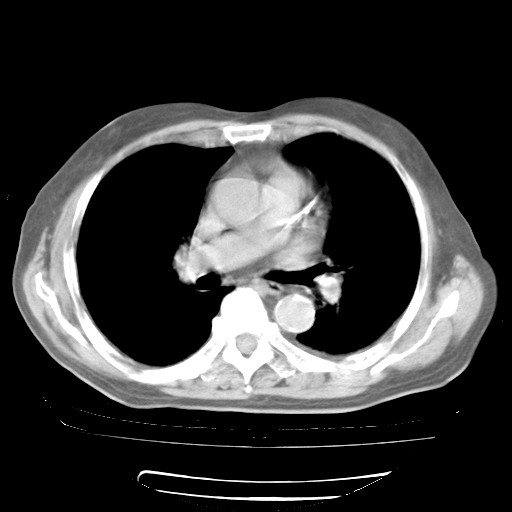

4月28日肺部CT——再次出现类似去年5月9日——透光度降低,“间质性”改变。